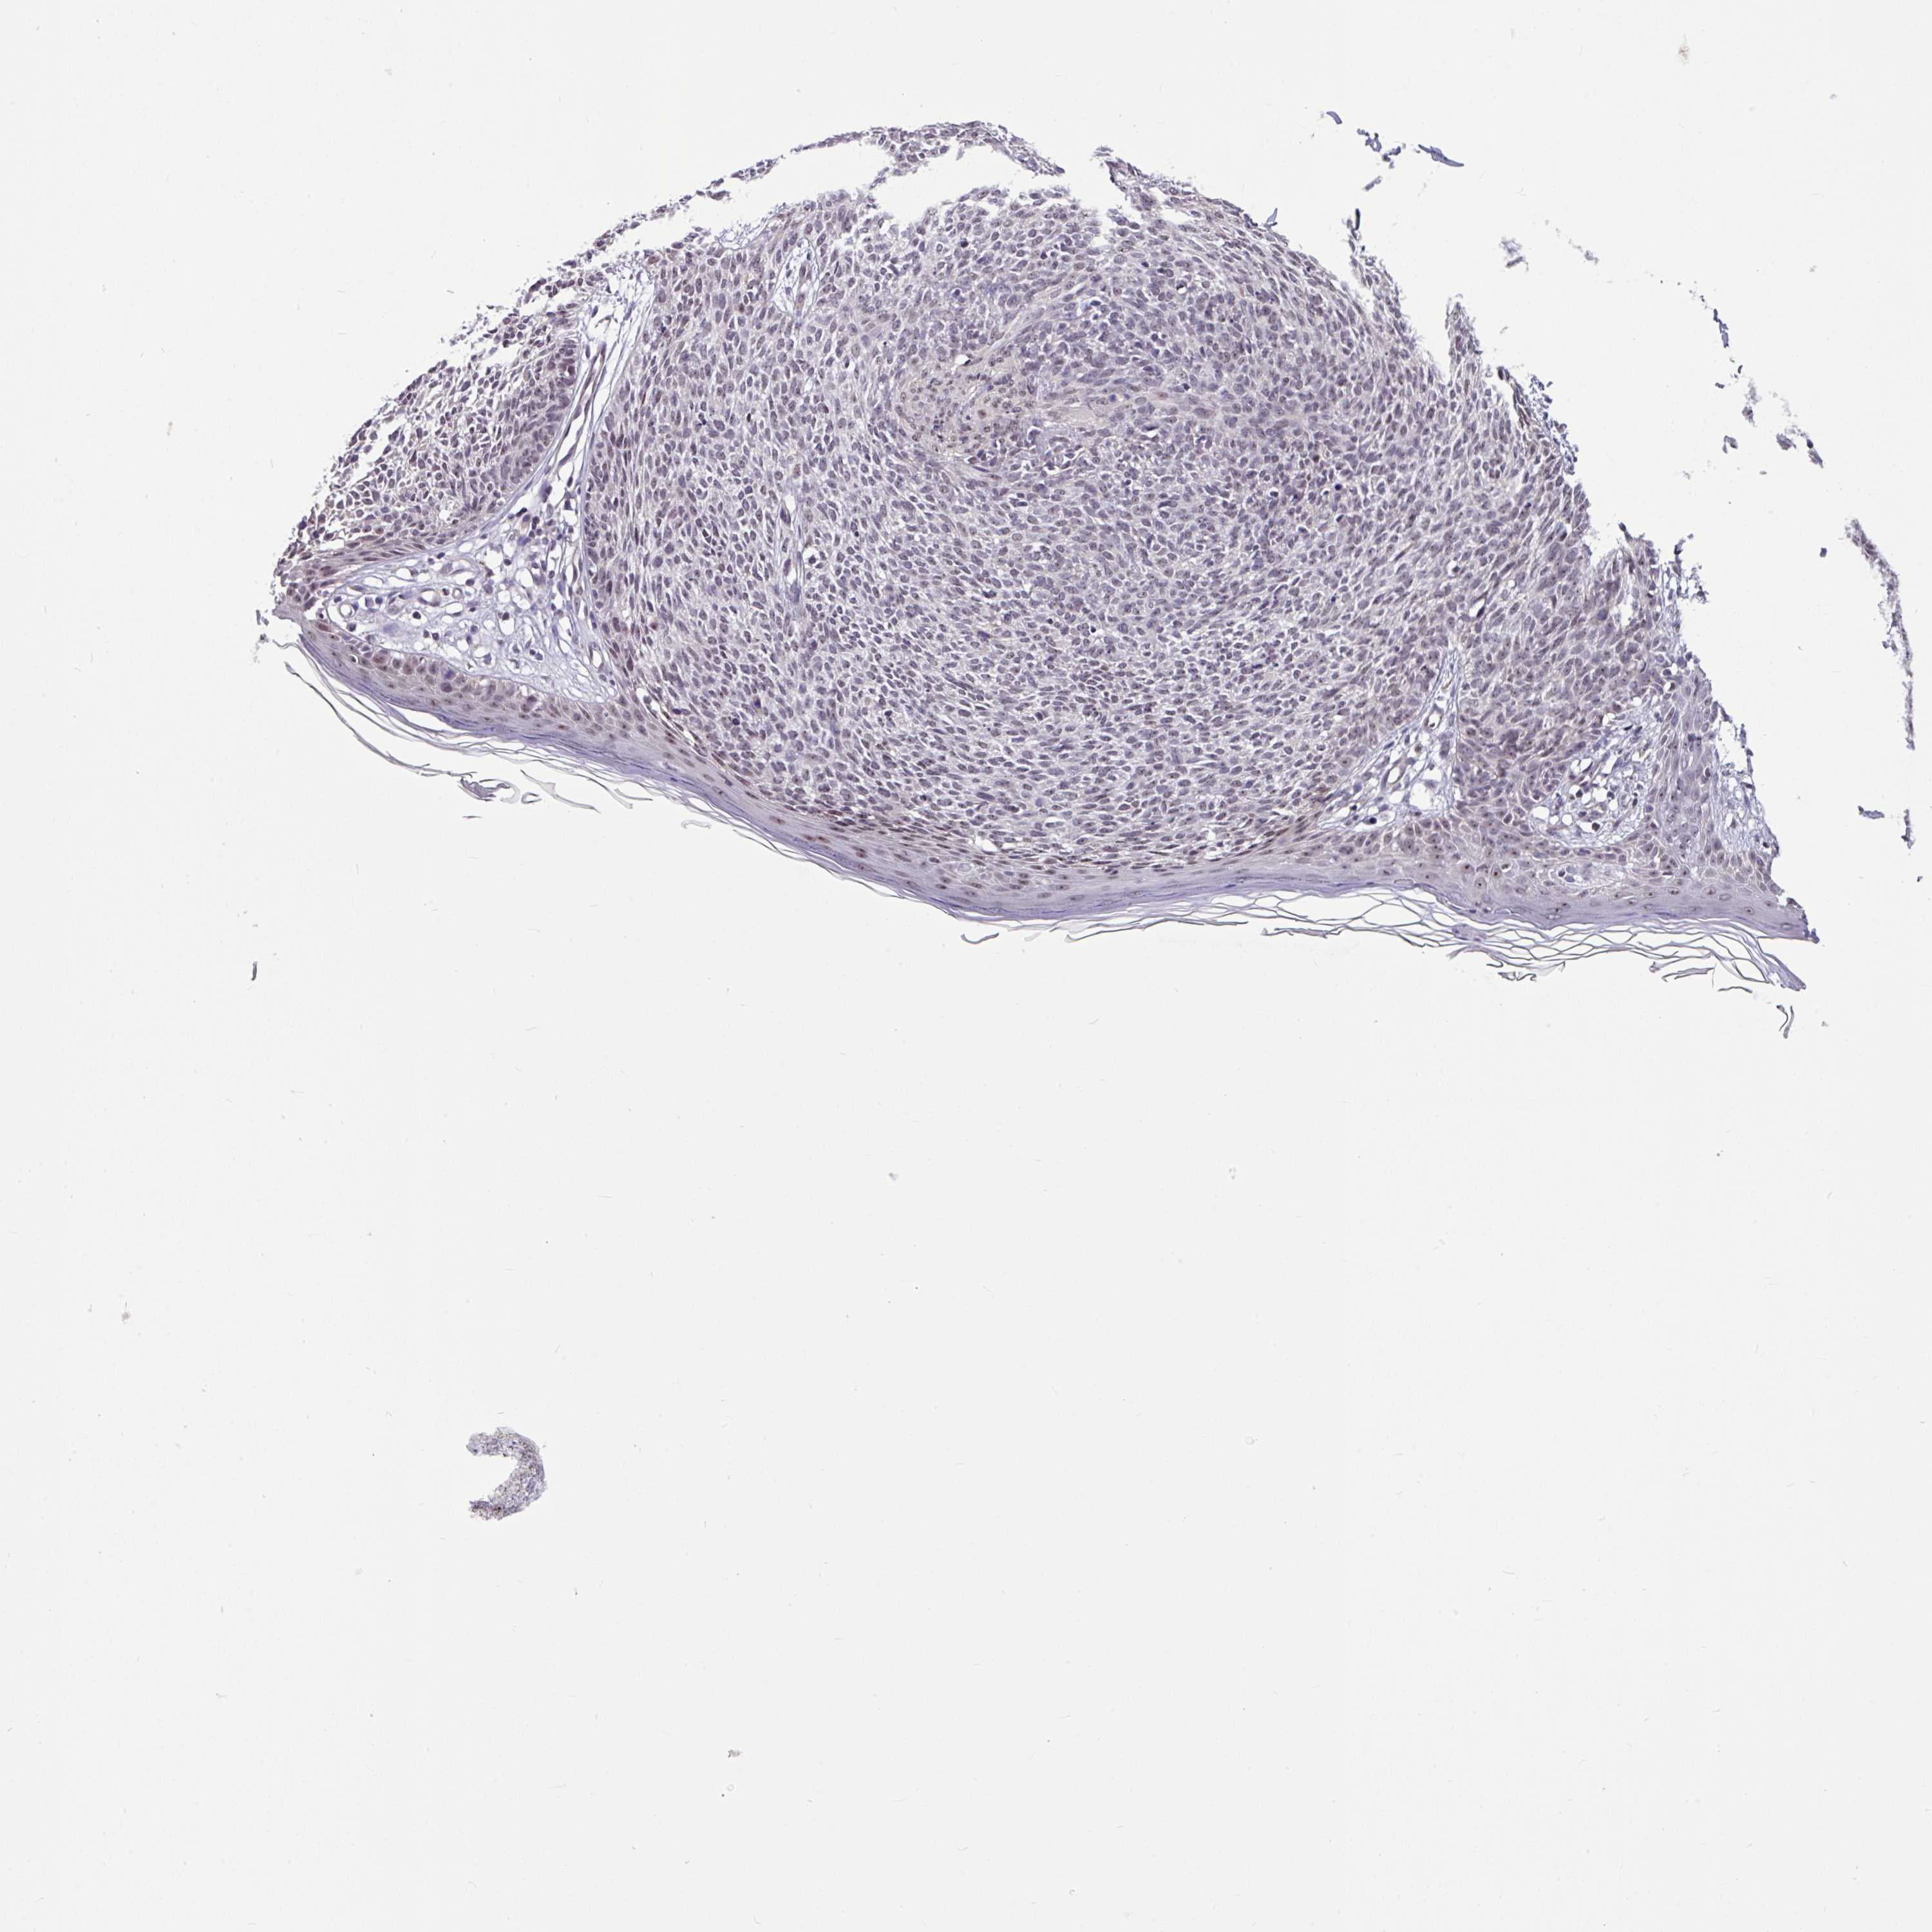

SKIN CANCER - Protein expressioni

A mouse-over function shows sample information and annotation data. Click on an image to view it in a full screen mode. Samples can be filtered based on level of antibody staining by selecting one or several of the following categories: high, medium, low and not detected. The assay and annotation is described here.

Each image is clickable and will lead to virtual microscopy that enables deeper exploration of all samples and also displays staining intensity scores, fraction scores and subcellular localization as well as patient and tissue information for each sample.

Antibody HPA052378

Staining

High

Intensity

Strong

Quantity

>75%

Location

Nuclear

Basal cell carcinoma